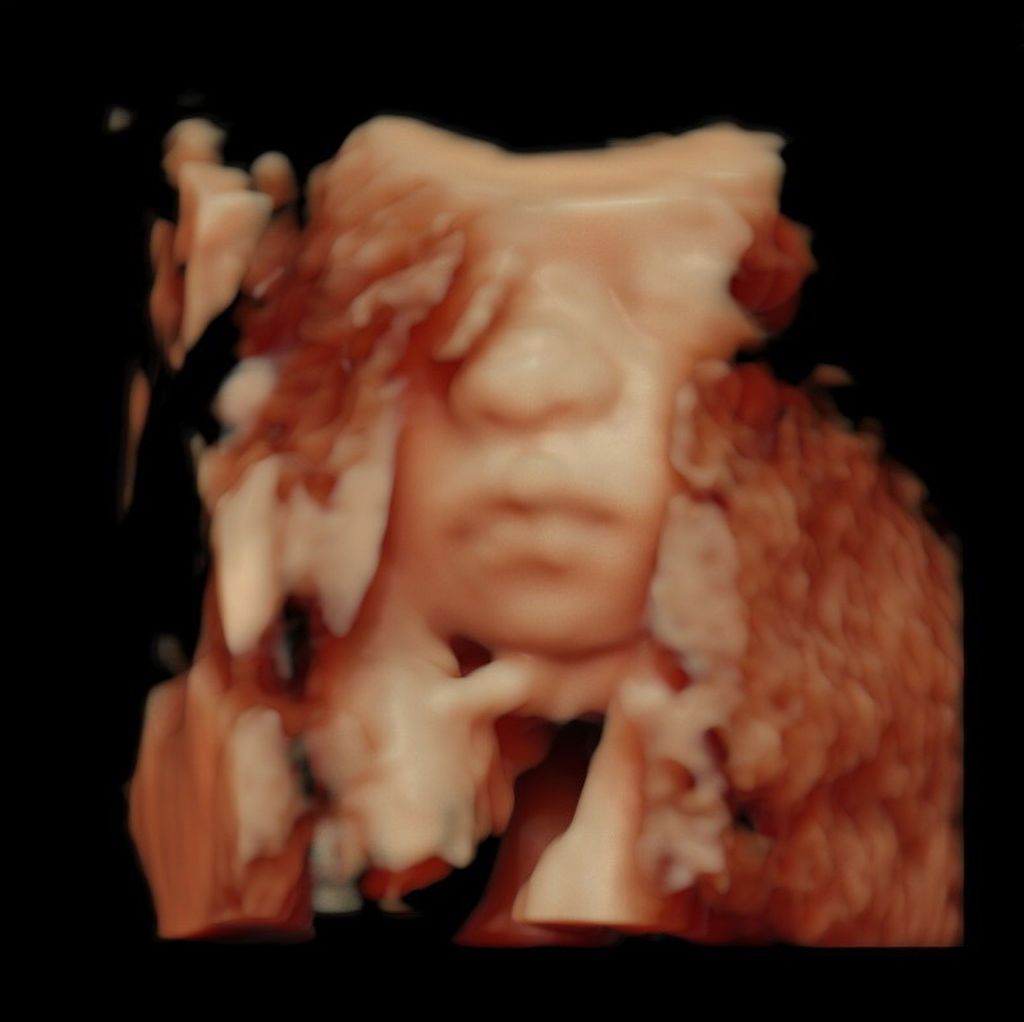

Η ίδια θέλοντας να «βουλώσει» τα στόματα αρκετών που σχολίασαν την κοιλιά της και δη ότι το μωρό μάλλον είναι αρκετά στριμωγμένο εκεί μέσα, δημοσίευσε για πρώτη φορά 3D υπέρηχο από το μωράκι της, γράφοντας ότι έχει πάρει τα χειλάκια του μπαμπά του (δείτε τις φώτο στη gallery παρακάτω).